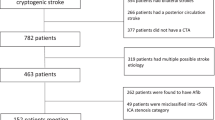

Of the 3061 patients with acute ischemic stroke between January 2013 and December 2017, 657 (21.5%) were classified as having large artery atherosclerosis according to the TOAST classification. Among the latter, 117 (17.8%) patients had symptomatic pICA disease. After excluding patients with complete occlusion of the carotid artery, those with no DWI or MRA data, and those with poor MRA quality, the final study population included 93 patients.